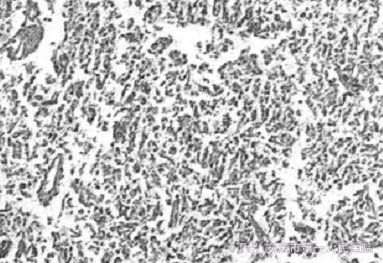

临床诊断:肺神经内分泌癌、异位性ACTH综合征及继发性糖尿病。入院第30天行左肺下叶切除术。术后病理:左肺下叶支气管旁灰粉色结节2.5 cm×1.9cmx 1.2cm,下叶内散在分布直径O.154—0.5 cm大小结节10余枚,诊断为高分化神经内分泌癌(图1)。神经特异性烯醇化酶(+),嗜铬颗粒素A(+),降钙素(+),ACTIJ(±),呈腺样和梭形细胞分化。术后患者一般状态迅速改善。在停用降压药的情况下血压稳定在140/85 mm Hg以下。肌无力症状明显改善,1周后即可自行下地活动,精神状态及反应均好转,满月脸较术前明显减小:术后1周血钾4.43 mmol/L,空腹血糖4.6 mmol/L,尿糖(一);术后2周血皮质醇节律8:00,16:00,24:00分别为247μg/L、305肛班μg/L、198μg/L,ACTH 151 ng/L,24h尿皮质醇60.9μg。术后3周患者出院。